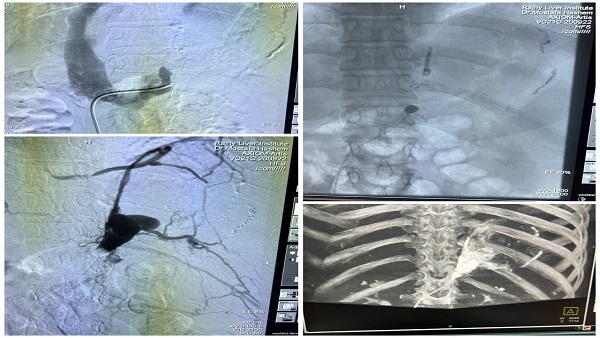

وفى السياق ذاته أعلن الدكتور علاء عطية عميد كلية الطب ورئيس مجلس إدارة مستشفيات أسيوط الجامعية عن تحقيق مستشفيات جامعة أسيوط انجاز وسبق علمي جديد من خلال نجاح فريق طبي بوحدة الأشعة التداخلية بقسم الأشعة بمستشفيات جامعة أسيوط بعمل تقنية غلق دوالي المعدة عن طريق الأشعة التداخلية باستخدام البالونات ولأول مرة على مستوى مستشفيات الجمهورية والذى يضاف إلى سجل انجازاتها الطبية والعلاجية وتأكيدًا على التعاون والتكامل بين المستشفيات فى مختلف التخصصات لتقديم وتطوير الرعاية الطبية المقدمة للمرضى المترددين عليها من مختلف محافظات الصعيد.

أوضح الدكتور شريف كامل مدير مستشفى الراجحى للكبد والجهاز الهضمى أنه تمت إجراء العملية بوحدة الأشعة التداخلية بمستشفى الراجحى الجامعى للكبد بقيادة الدكتور مصطفى هاشم رئيس قسم الأشعة التشخيصية والتداخلية وضم الفريق الطبي كلًا من الدكتور رامي محمد مدرس الأشعة التشخيصية والتداخلية، والدكتور سيد حسن مدرس الأشعة التشخيصية والتداخلية، والدكتور ممتاز ثابت مدرس الأشعة التشخيصية والتداخلية، والدكتور مصطفى أحمد مدرس مساعد الأشعة التشخيصية والتداخلية.

وأوضح الدكتور مصطفى هاشم أن هذه التقنية الحديثة تستخدم فى علاج حالات معينة من دوالي المعدة والتي لا يمكن التعامل معها من خلال مناظير المعدة وتتم ولأول مرة بمستشفيات جمهورية مصر العربية، موجهًا كل الشكر لطاقم التمريض وطاقم الفنيين والمساعدين بوحدة الأشعة بمستشفى الراجحى.